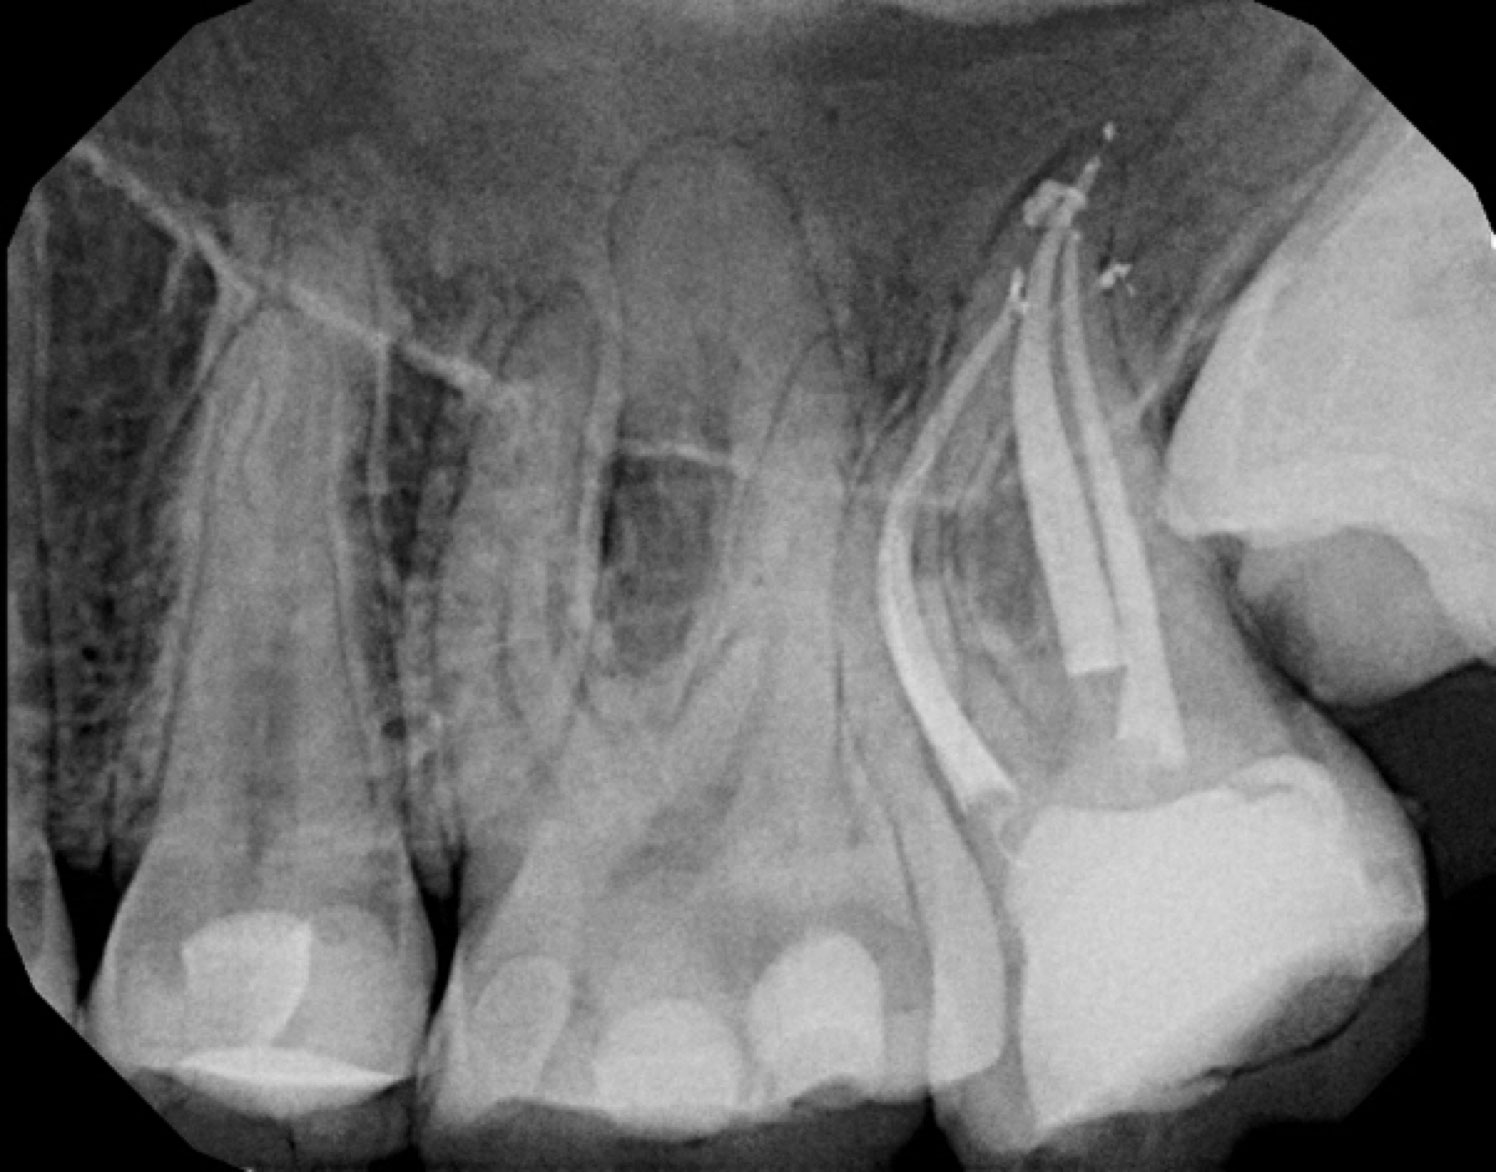

At our clinic, we use advanced imaging, microscope operating techniques, combined with our years of specialist training to diagnose and treat complex cases – all in a calm and supportive environment.

Our team of root canal specialists in Central London focuses on the identification and treatment of severe tooth pain. The types of procedures we do are usually highly complex and can include everything from emergency endodontic procedures to root end surgery or apicectomy. Thanks to our specialist team and state-of-the-art clinic, we can treat: